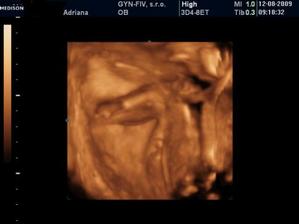

3.6. Uzasny 3D ultrazvuk...Videli sme nasho mimiska... Meriame bez noziciek 10 cm a s nozickami skoro 15 cm... 🙂 A doktor nas prekvapill, ze vraj to bude chlapcek... 🙂 14.7. morfologicky ultrazvuk, vsetko zatial vyzera v poriadku - tesime sa na Andrejka 🙂 12.8. 3D ultrazvuk - ma to 35 cm a 900 gramov, kto je to? No predsa ja Andrejko... 🙂